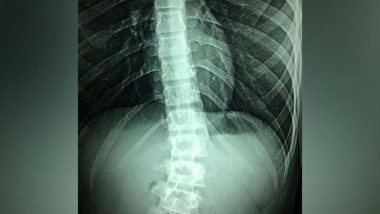

Spinal cord stimulation involves a device that is implanted under the skin. The device delivers electrical stimulation to the spinal cord to cut off pain signals to the brain.